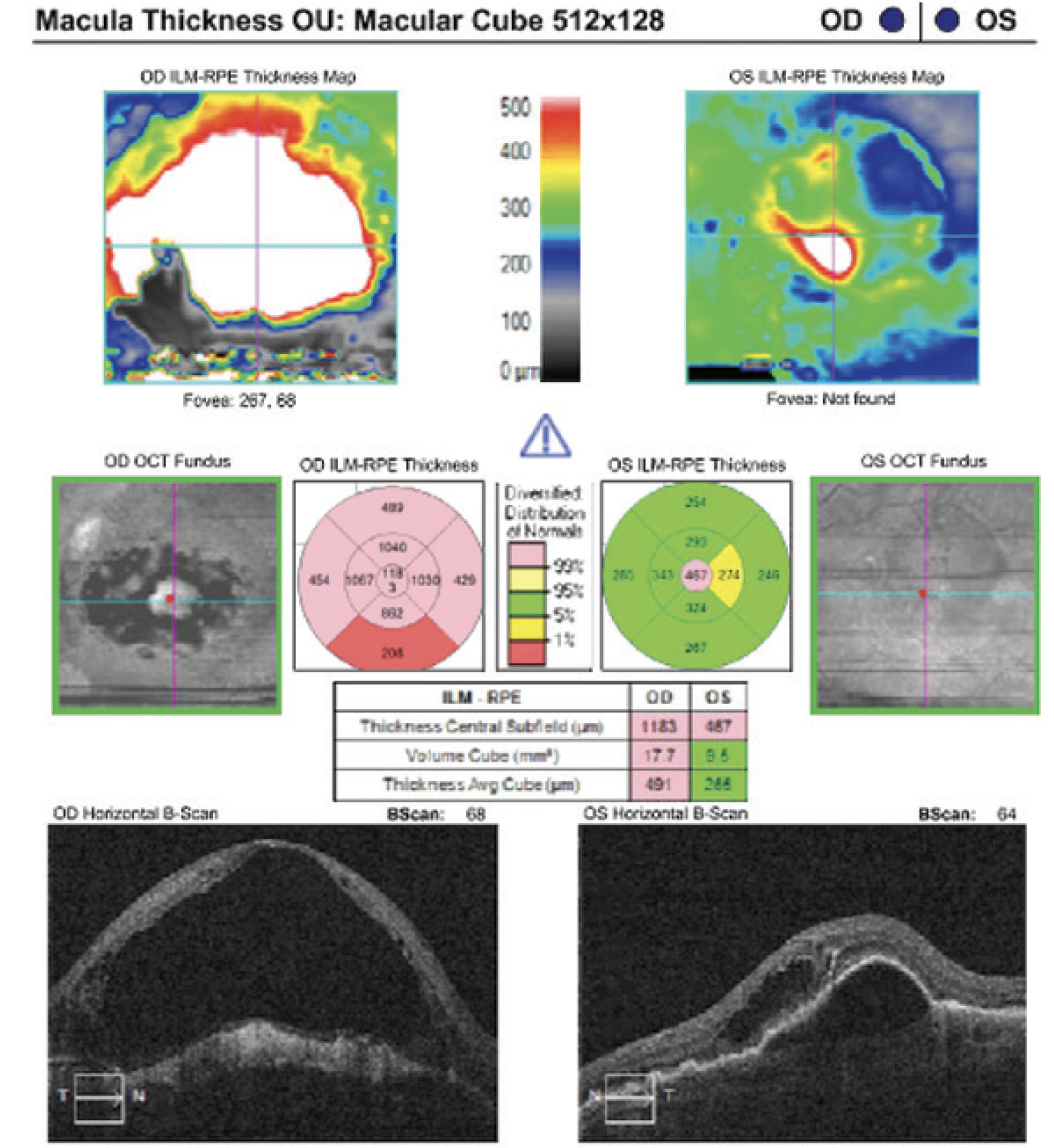

- Initial visit imaging showed active exudative neovascular AMD OS and a large disciform scar OD (Figure 1)

Figure 1. Baseline imaging in an 86-year-old woman referred for anti-VEGF agent switch.